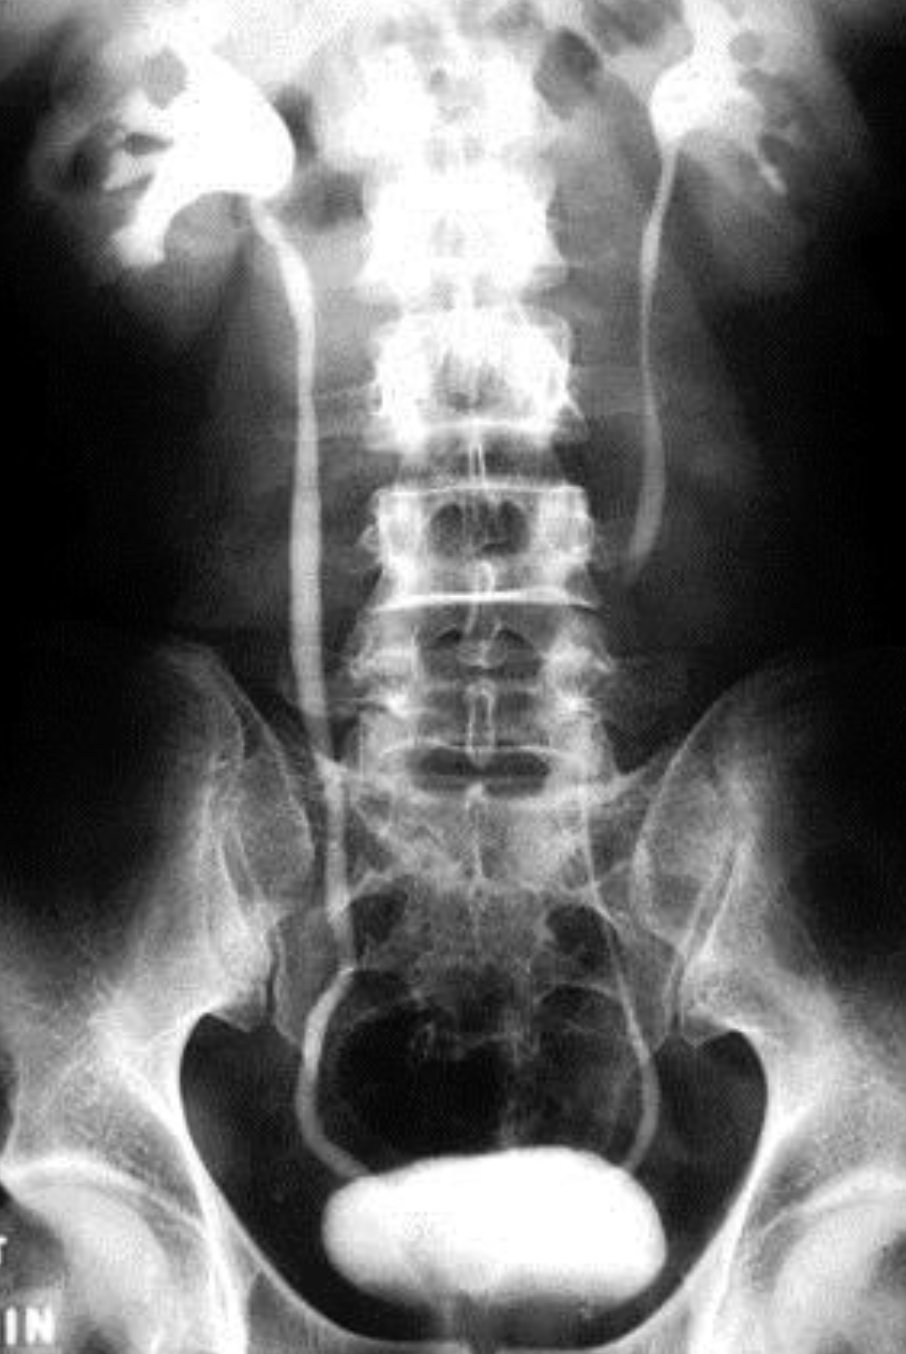

IMAGING: i.v.Pyelogram, u/s, CT (with contrast)

i.v. pyelogram (I.V.P)

Role of Imaging

Plain x-ray

Ultrasonography

CT

Intravenous pyelography (IVP)

Micturating cystourethrography